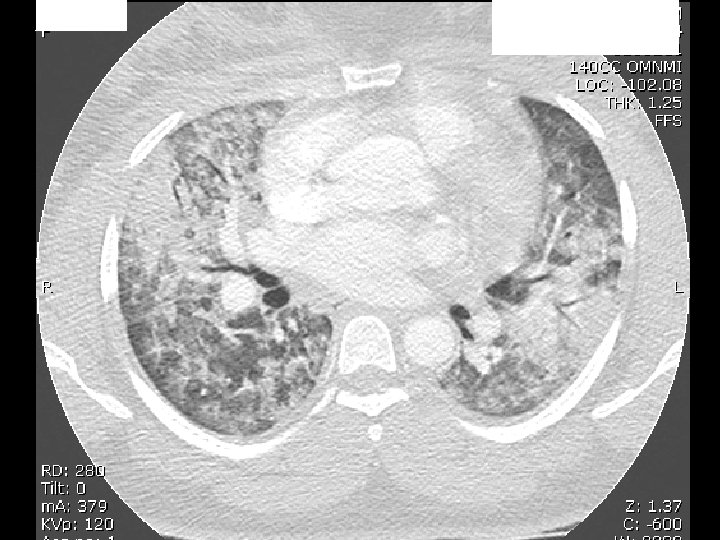

• Diffuse bilateral infiltrates – Patchy, confluent – Alveolar, ground ‐ glass • In contrast to CHF, no prominence of. . – Cardiomegaly – Pleural effusion – Widened vascular pedicle

ARDS Triggers primary vs secondary • Primary Direct lung injury (eg aspiration, • pneumonia, contusion, inhalation) – Patchy – If it doesn’t evolve into SIRS/MODS, Outcome better than secondary

ARDS Triggers primary vs secondary • • Secondary Lung is one of many organs involved in SIRS/MODS (sepsis, pancreatitis, hypotension) – Diffuse – Outcome worse than primary